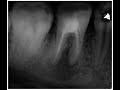

Пульпотомия зуба 8.4 в условиях общего обезболивания